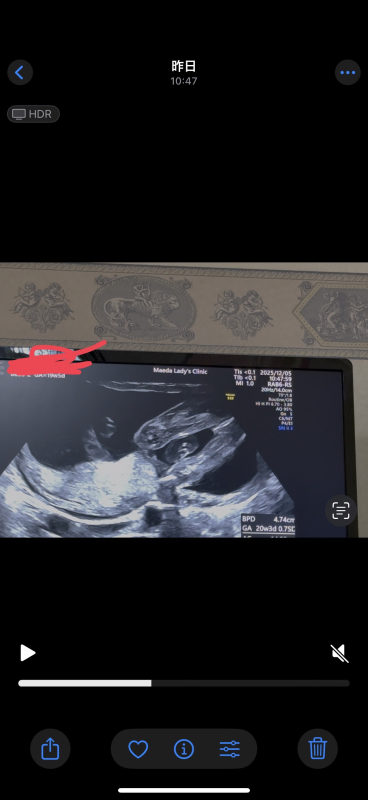

21週になりました!

ですが、まだ性別がわかりません。

いつもエコー見て検索魔になってしまい。

もし分かるのであれば教えて欲しいです

お腹の赤ちゃんの性別についてですね。

なので断言はできませんが、足と足の間男の子シンボルがはっきりと映っていなそうに感じたのと割れ目が見られるようにも思いましたので、女の子の可能性があるのではと思いました。

しかしはっきりとはわからないため、また次の健診の際に先生へご確認ください。